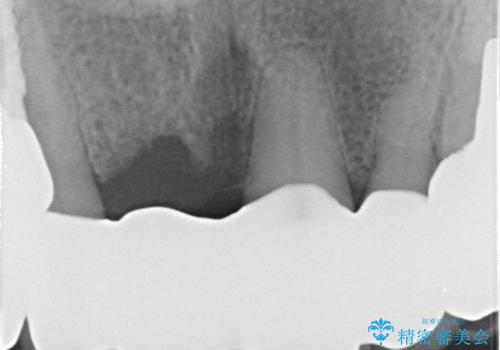

- 前歯がグラグラするとの事で来院。

精査したところ、右上の前歯はかなり動揺があり保存できない状態でした。

右上の前歯の抜歯を行い、ブリッジの仮歯を入れ、動揺が無くなるのを確認した後、ジルコニアクラウンブリッジを入れました。